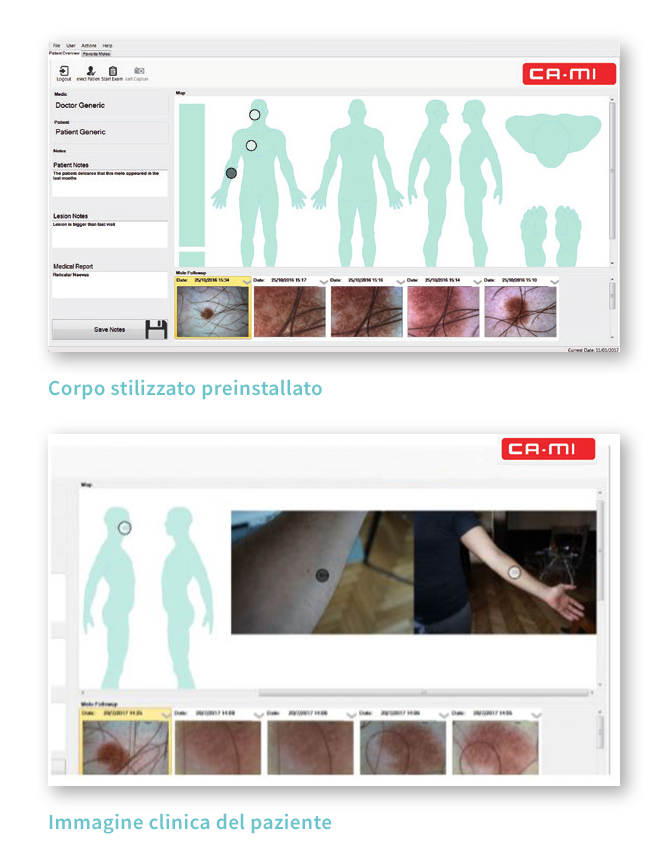

Inserendo le immagini nella body map del paziente , l’utente ha a disposizione un follow up completo per ogni neo esaminato;

Le immagini cliniche, acquisite con la camera wireless, sono automaticamente memorizzate nella cartella del paziente e possono essere usate per ottenere una body map del paziente molto realistica;

Body map: lo strumento di memorizzazione delle immagini

La Body Map è lo strumento di archiviazione immagini semplice, intuitivo e organizzato. Ogni immagine dermoscopica acquisita può essere posizionata sulla figura presalvata del paziente o sulla foto clinica del paziente ottenuta con la Total Body Camera, trascinandola nella corretta posizione. Quando sono presenti più immagini dermoscopiche dello stesso nevo, possono essere salvate nello stesso punto della mappa, creando un unico follow up della lesione.

La visualizzazione delle immagini dermoscopiche acquisite è semplice: cliccando sulla circonferenza desiderata, tutte le immagini riferite a quella lesione appaiono nel pannello sottostante, corredate dalle informazioni inserite. La Body Map e le foto cliniche del paziente sono entrambe navigabili e permettono di ingrandire e distinguere i nevi vicini.